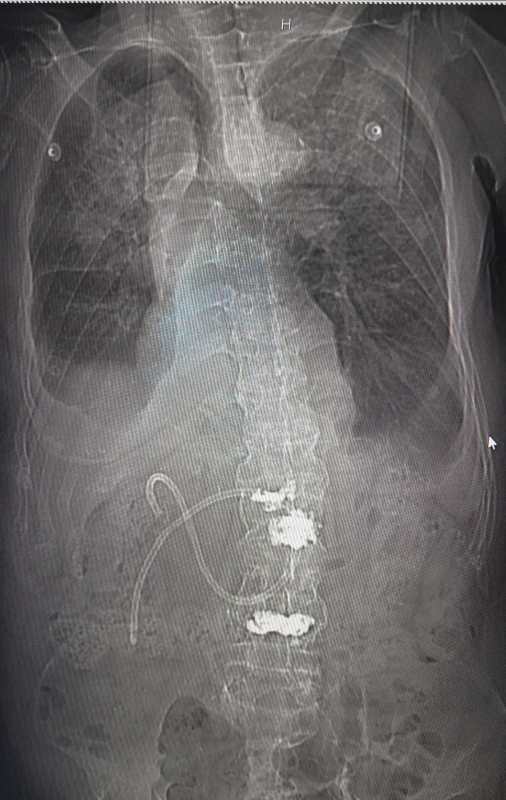

ct檢查判斷鼻腸管置管成功

床旁超聲被喻為看得到的“聽診器”,開展床旁超聲引導(dǎo)下鼻腸管置入術(shù),與傳統(tǒng)的鼻腸管盲插術(shù)形成有效互補。該技術(shù)利用超聲優(yōu)勢,在床旁進行實時引導(dǎo),準(zhǔn)確通過幽門后進行腸內(nèi)營養(yǎng)置管。相比傳統(tǒng)方法更加安全穩(wěn)定,無副作用。在床旁超聲確認通過后僅需攝片一次確認鼻腸管位置,留取影像學(xué)資料,極大減少了患者及醫(yī)護人員接觸輻射的時間,降低了因盲插而發(fā)生并發(fā)癥的可能,更好的保證了患者的安全,有效節(jié)省了人力資源。